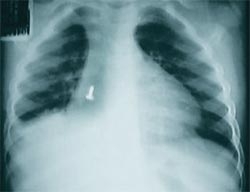

Encaminhada ao Hospital Infantial Jeser Amarante, da cidade vizinha de Joinville, a criança não corre risco de vida. A equipe médica detectou a presença de um pequeno caco de vidro no organismo do menino e aguarda que o material seja expelido de forma natural.